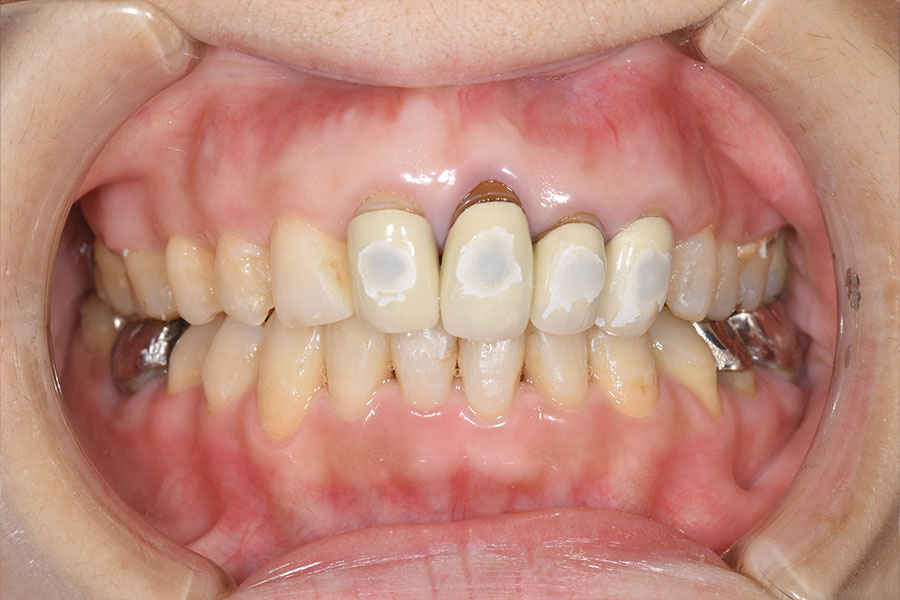

Before -正面-

After -正面-

| 施術内容 | 金属アレルギー予防を目的に、金属フリーの自費補綴へ変更。適合性・清掃性・審美性の向上が得られています。 |

|---|---|

| 治療期間 | 約4ヶ月 |

| 費用 | ハイブリットクラウン ハイブリットインレー 693,000円 |

| リスク・副作用 | 治療にともない、歯の破折や歯質の削合、場合によっては抜歯が必要となることがあります。また、金属や補綴物を除去する際に、完全に除去できない場合もあります。 |